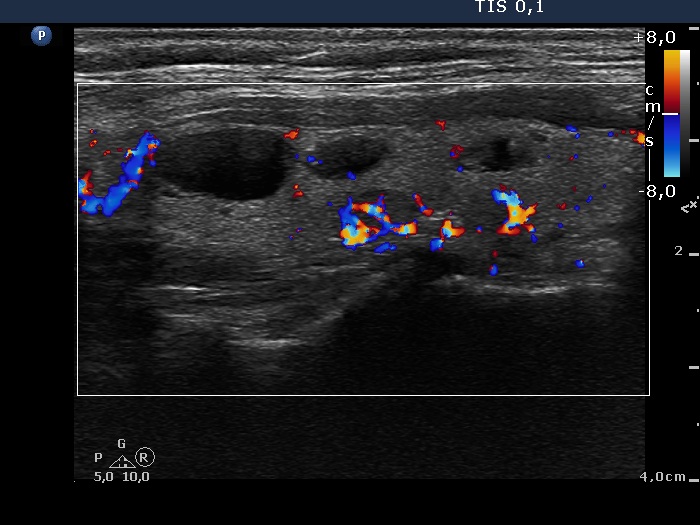

Ultrasonography: The thyroid was echonormal and contained several nodules with different echogenicities including a hypoechogenic one in the ventromedial part of the left lobe. This lesion presented a lobulated margin and a type 1 vascular pattern.